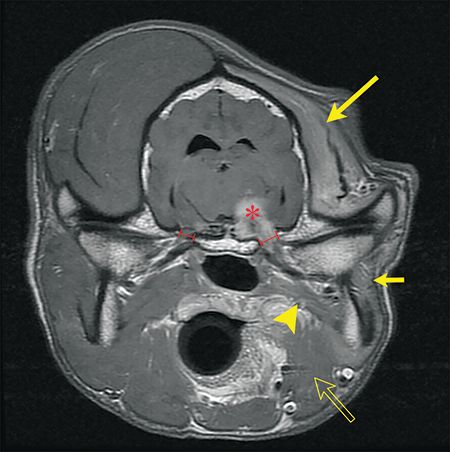

A common cause of unilateral trigeminal nerve dysfunction is a nerve sheath neoplasm. Other causes of trigeminal nerve dysfunction include trauma, infectious or noninfectious neuritis, and other forms of neoplasia such as lymphoma. A complete physical and neurological examination may help narrow the differential diagnoses. Magnetic resonance imaging (MRI) of the head is the best way to establish a definitive diagnosis. With trigeminal nerve sheath neoplasms, MRI findings include an enlargement of the trigeminal nerve or its main branches, which display contrast enhancement, enlargement of the oval foramen from pressure necrosis from the expansile growth of the mandibular nerve, compression or invasion of the pons by the neoplasm, denervation atrophy of the masticatory muscles, and effusion in the tympanic cavity (middle ear) (Figure 3).

Figure 3. A transverse T1-weighted post-contrast MRI of Max's brain. A trigeminal nerve sheath neoplasm is compressing the brain stem (red asterisk) and is continuing along the mandibular branch as it exits via the oval foramen. Note the enlargement of the left oval foramen in comparison to the right. There is pronounced atrophy of the temporalis (large yellow arrow), masseter (small yellow arrow), digastricus (open yellow arrow) and pterygoid (yellow arrowhead).